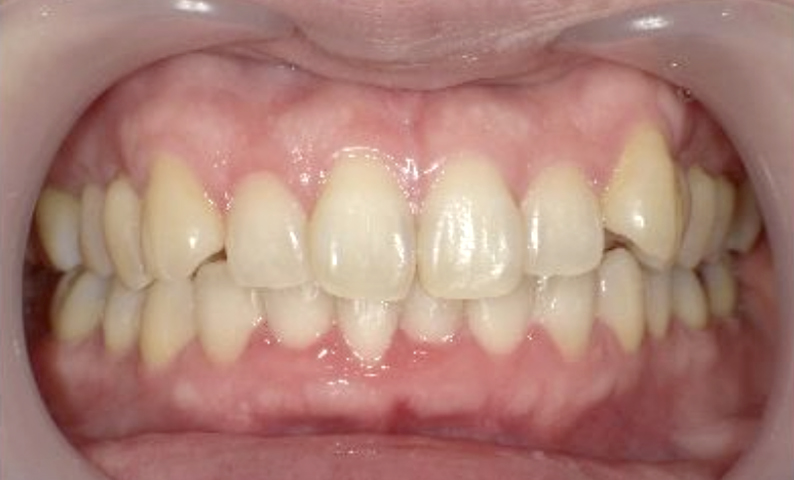

症例_002 上顎だけの部分矯正

治療期間:7ヶ月金額:30万円+税女性前歯のガタガタ上の前歯だけ

| Before | After |

|---|---|

|